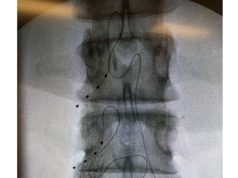

Regarding the intervention itself, the Axium neurostimulation system (Abbott) was used to place electrodes at the target DRGs. At baseline, the regional distribution of each patients’s primary pain area, including intensity, was mapped. Measures of functioning, quality of life and mood were also assessed. Follow-ups were conducted at one, three, six and 12 months’ post-permanent implant; repeating baseline assessments and evaluating patients for any adverse events. Outcomes at the end of the trial stimulation period were quantified by the percentage change in the VAS scores relative to baseline, to assess the change from baseline to each follow-up visit.

Of the 66 subjects enrolled, failed back sur gery syndrome, peripheral nerve injury, and complex regional pain syndrome formed the lar gest aetiologies. Permanent implants were placed in 56 of the subjects (86.2% of those originally recruited).